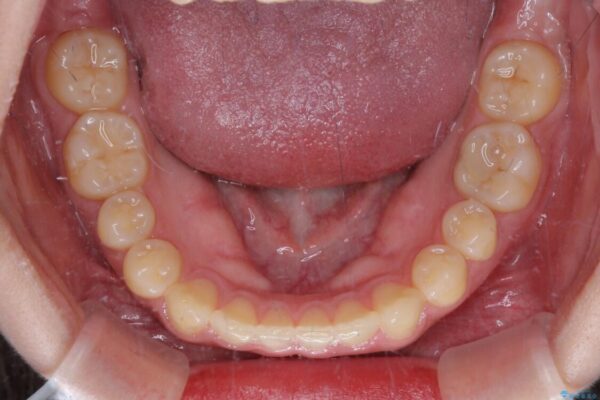

治療前

• 治療途中の奥歯と矯正治療の後戻り インビザライン・ライトによる矯正治療 治療前画像

治療途中

• 治療途中の奥歯と矯正治療の後戻り インビザライン・ライトによる矯正治療 治療途中画像